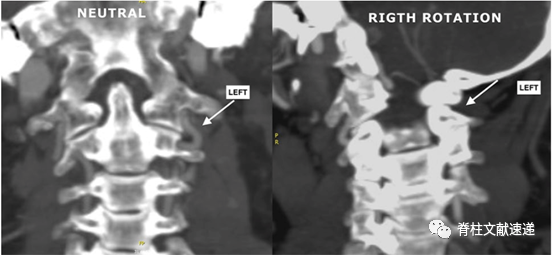

4) 头颈部血管CTA可评估骨性结构和血管形态以及两者的关系。头部不同位置的CTA,可见椎动脉的血流情况。

图注:CTA冠状位:左图为头部中立位时,双侧椎动脉可见;右图为头部右转时,右侧椎动脉可见,左侧V3段椎动脉闭塞。